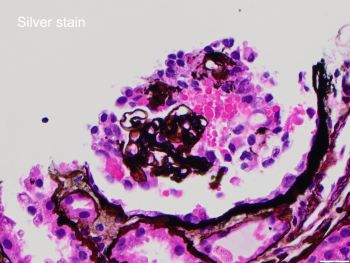

A 42-year-old African-American female with a history of systemic lupus erythematosus with acute kidney injury (creatinine 2.7 mg/dL), proteinuria (1064 mg/24 hr), and no hematuria, was admitted for lupus encephalitis. Renal biopsy by light microscopy showed that most glomeruli had no lesions (Figure 1) with one glomerulus with glomerular tuft collapse, and podocyte hypertrophy/hyperplasia (Figure 2). There was positive mesangial staining by immunofluorescence with IgG, IgM, IgA, C3, C1q, and light chains (Figure 3). Electron microscopy findings included diffuse foot process effacement, and mesangial electron-dense deposits (Figure 4).